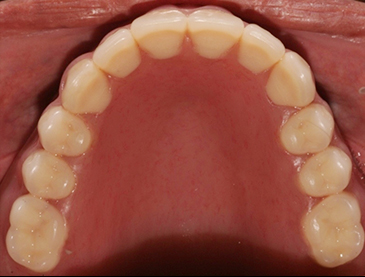

Fully edentulous clinical cases